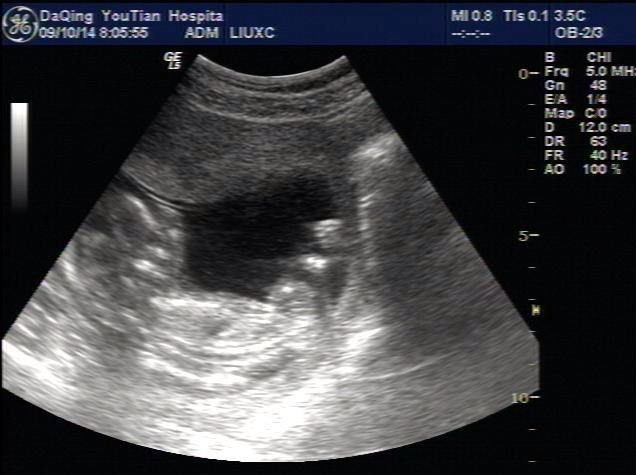

B超超声检查是利用声波反射,得到不同的回声来形成影像,跟朝水里扔石头听回声来测深度差不多一个道理。

超声检查是利用声波反射成像,没有辐射!

B超主要筛查腹腔、盆腔内器官是不是有病变,包括:乳腺、甲状腺、肝脏、肾脏、胰腺、胆囊、脾脏、膀胱、子宫、卵巢等。心脏部位的检查也常会用到B超。